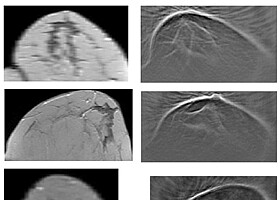

Brustkrebsdetektion durch 3D-Ultraschall-Computertomografie

Forschende des KIT entwickeln neues bildgebendes Verfahren zur Brustkrebsfrüherkennung.

Bilderzeugung für tomographische Verfahren

Bilddaten-Rekonstruktion mit Compressive Sampling erzeugt qualitativ hochwertige Ergebnisse aus wenigen Bildern.